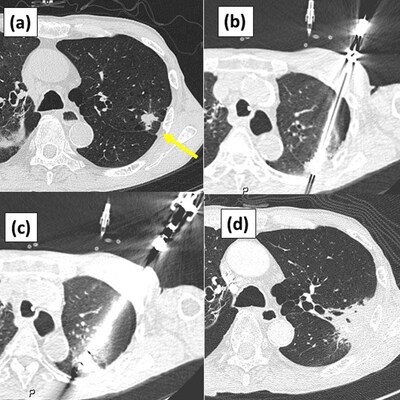

1 Image citation: "Figure 2 from Nomori H, Yue C, Iguchi H, Kashihara K, Wada R, Saito T. Long-term outcomes of combination therapy with stereotactic body radiation therapy plus cryoablation using liquid nitrogen for stage I non-small cell lung cancer with tumors ≥ 2 cm. PLOS ONE. 2025; 5:1–12. https://doi.org/10.1371/journal.pone.0332893, distributed under the terms of the Creative Commons Attribution 4.0 International License (CC BY 4.0)"